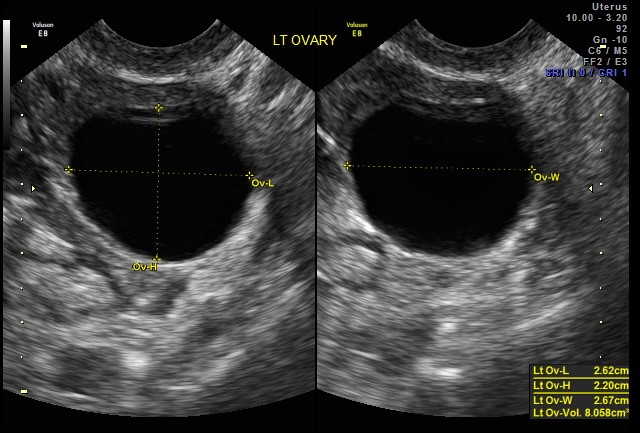

(image: Ultrasound of left ovary with follicle, via the SoR)